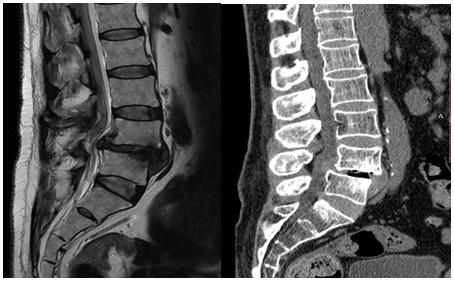

حيث تبين بعد مناظرة الأشعة المقطعية وأشعة الرنين المغناطيسي وجود تزحزح فقاري قطني مع كسر تحللي بعنق الفقرة القطنية الرابعة، مما أدى إلى ضغط شديد على جذور العصب النسئ بالطرفين الأيمن والأيسر.